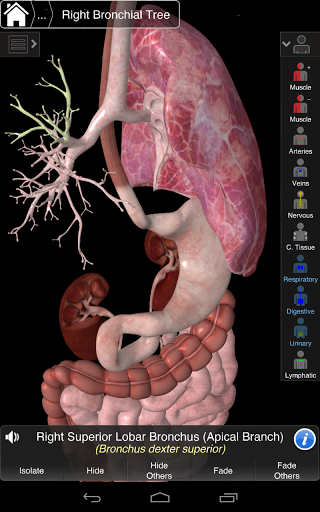

Essential Anatomy 3 representa lo último en tecnología 3D innovadora y diseño innovador. Un motor de gráficos 3D de vanguardia, creado a medida por 3D4Medical desde cero, alimenta un modelo anatómico altamente detallado y ofrece gráficos de calidad excepcional que ningún otro competidor puede lograr.

La aplicación representa un enfoque único para el aprendizaje de la anatomía general. Los gráficos no tienen paralelo y hacen que el aprendizaje, a través del uso de contenido informativo y características innovadoras, sea una experiencia rica e interesante.

Esta aplicación incluye anatomía esencial para 10 sistemas:

⁃Respiratorio

⁃Digestivo

⁃Urinario

⁃Linfático

NUEVA TECNOLOGÍA 3D

Essential Anatomy 3 es receptivo, visualmente impactante y sin esfuerzo. La aplicación es totalmente en 3D, lo que significa que puedes ver cualquier estructura anatómica de forma aislada y desde cualquier ángulo.

---- Más de 4,000 estructuras anatómicas altamente detalladas

---- Nomenclatura latina para cada estructura anatómica